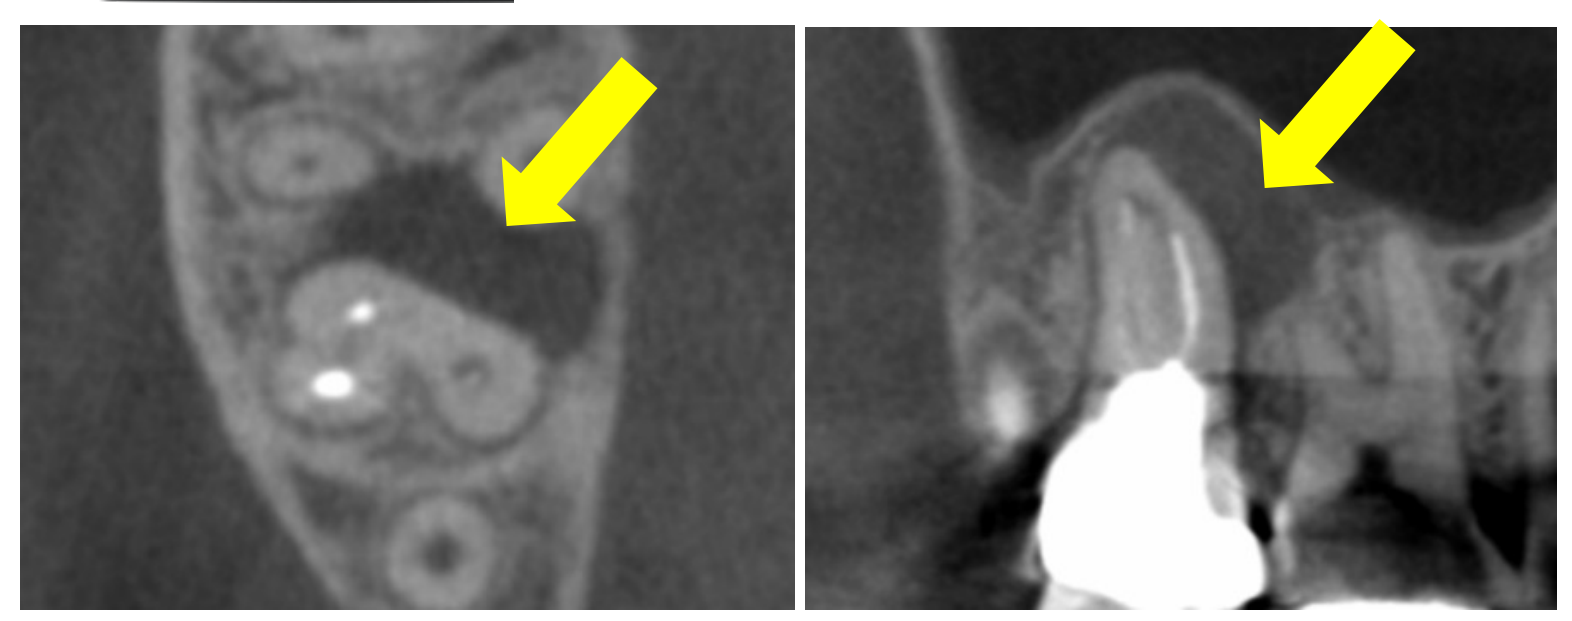

3. 正確な診断を可能にする歯科用CT

3D画像で根管の構造を立体的に把握

従来のレントゲンでは2次元の平面画像しか得られず、根管の正確な形状や病巣の広がりを把握することは困難でした。当院では、歯科用CTを導入し、歯の根の構造や周囲の骨の状態を3次元(3D)で立体的に診断します。これにより、診断の精度が格段に向上し、適切な治療計画を立てることが可能になります。複雑な根管の見落としを防ぎ、より確実な治療に繋がります。